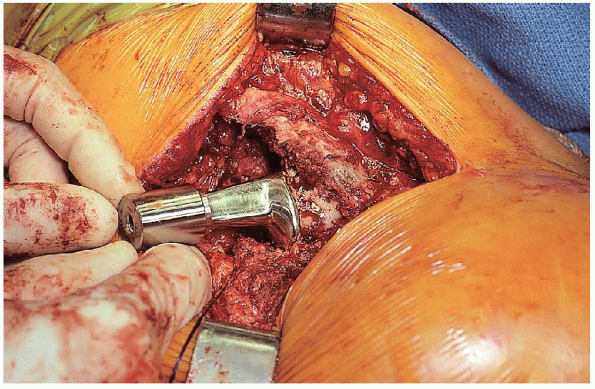

inserted using manual force and light taps with a mallet as it is fully seated to the level of the calcar cut (Fig. 22-23).

Stability is then reassessed using head and neck trials. The final

prosthetic head with the appropriate neck length is lightly impacted

onto the clean and dry trunnion, and the hip is reduced after clearing

all soft tissue from the opening of the acetabulum. Hip stability is

once more assessed before wound closure. The short external rotators

FIGURE 22-23. Insertion of the prosthesis.